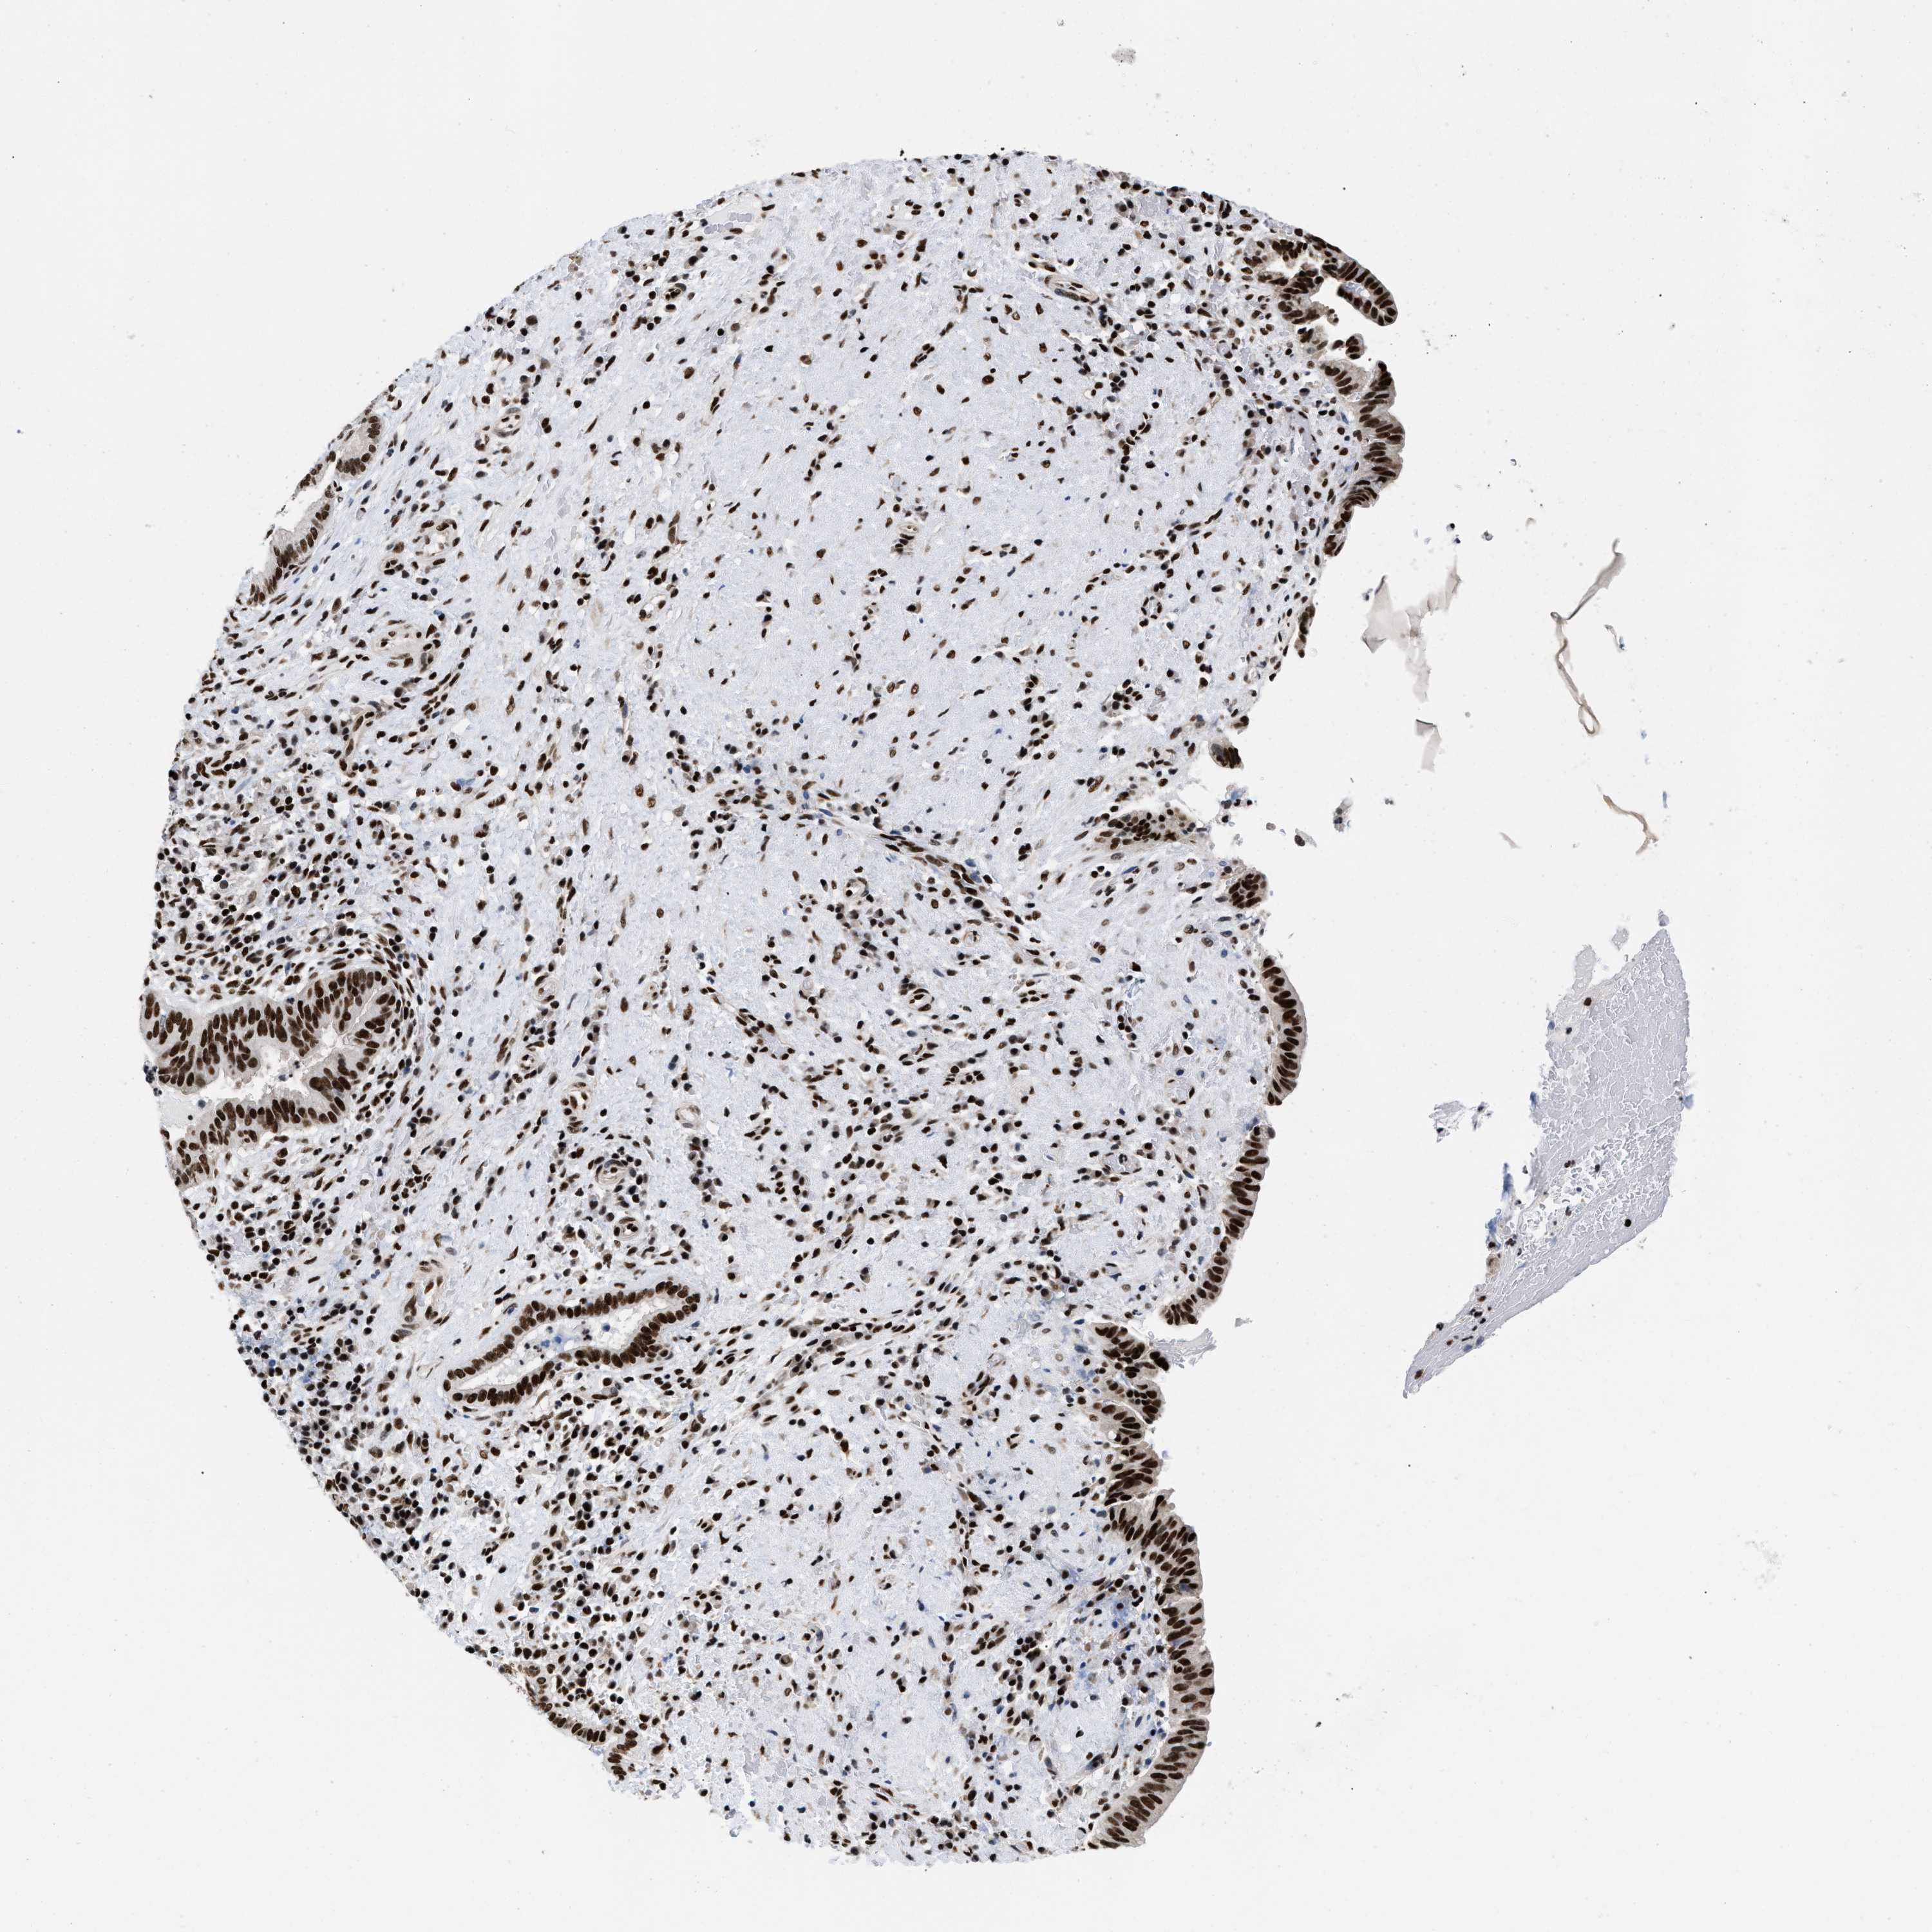

LIVER CANCER - Protein expressioni

A mouse-over function shows sample information and annotation data. Click on an image to view it in a full screen mode. Samples can be filtered based on level of antibody staining by selecting one or several of the following categories: high, medium, low and not detected. The assay and annotation is described here.

Note that samples used for immunohistochemistry by the Human Protein Atlas do not correspond to samples in the TCGA dataset.

Antibody stainingi

Antibody staining in the annotated cell types in the current human tissue is reported as not detected, low, medium, or high, based on conventional immunohistochemistry profiling in selected tissues. This score is based on the combination of the staining intensity and fraction of stained cells.

Each image is clickable and will lead to virtual microscopy that enables deeper exploration of all samples and also displays staining intensity scores, fraction scores and subcellular localization as well as patient and tissue information for each sample.

Antibody HPA019150

Antibody CAB003803

Staining

High

Medium

Low

Not detected

Intensity

Strong

Moderate

Weak

Negative

Quantity

>75%

75%-25%

<25%

None

Location

Nuclear

Cytoplasmic/membranous

Cytoplasmic/membranous,nuclear

Cholangiocarcinoma

Carcinoma, Hepatocellular, NOS